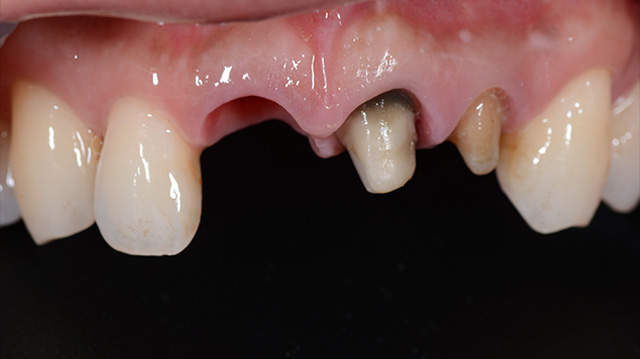

| 年代・性別 | 30代 男性 |

|---|---|

| 主訴 | 前歯の色が気になる |

| 治療期間 | 約1年 |

| 費用 |

仮歯 5,500円 × 2 ジルコニアクラウン 176,000円 × 3 インプラント 300,000円 インプラント仮歯 22,000円 サージカルガイド 70,000円 |